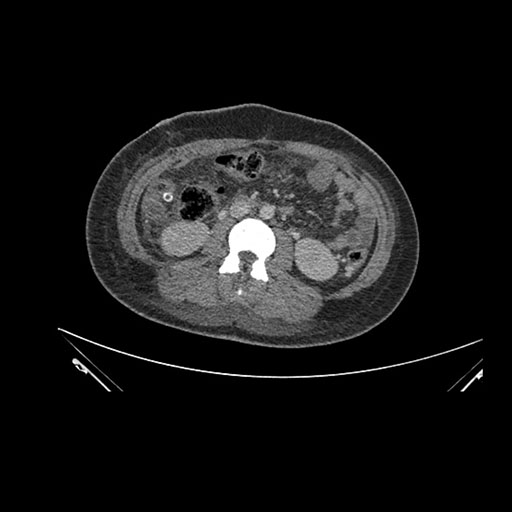

Imaging Analysis

Look through the patient's CT scan to identify any areas of concern for the necessary procedure.

Axial Arterial

Based on initial findings, which issue(s) would you be most concerned about?